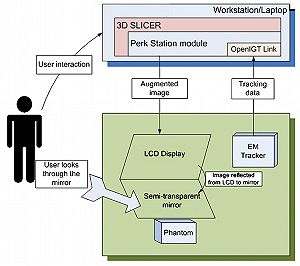

- 3.40 Openigtlink Interface for State Control and Visualisation of a Robot for Image-Guided Therapy Systems